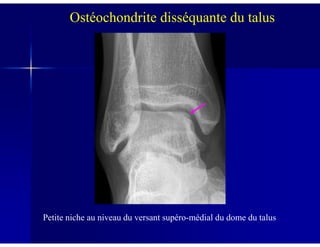

Ostéochondrite disséquante du talus

Petite niche au niveau du versant supéro-médial du dome du talus